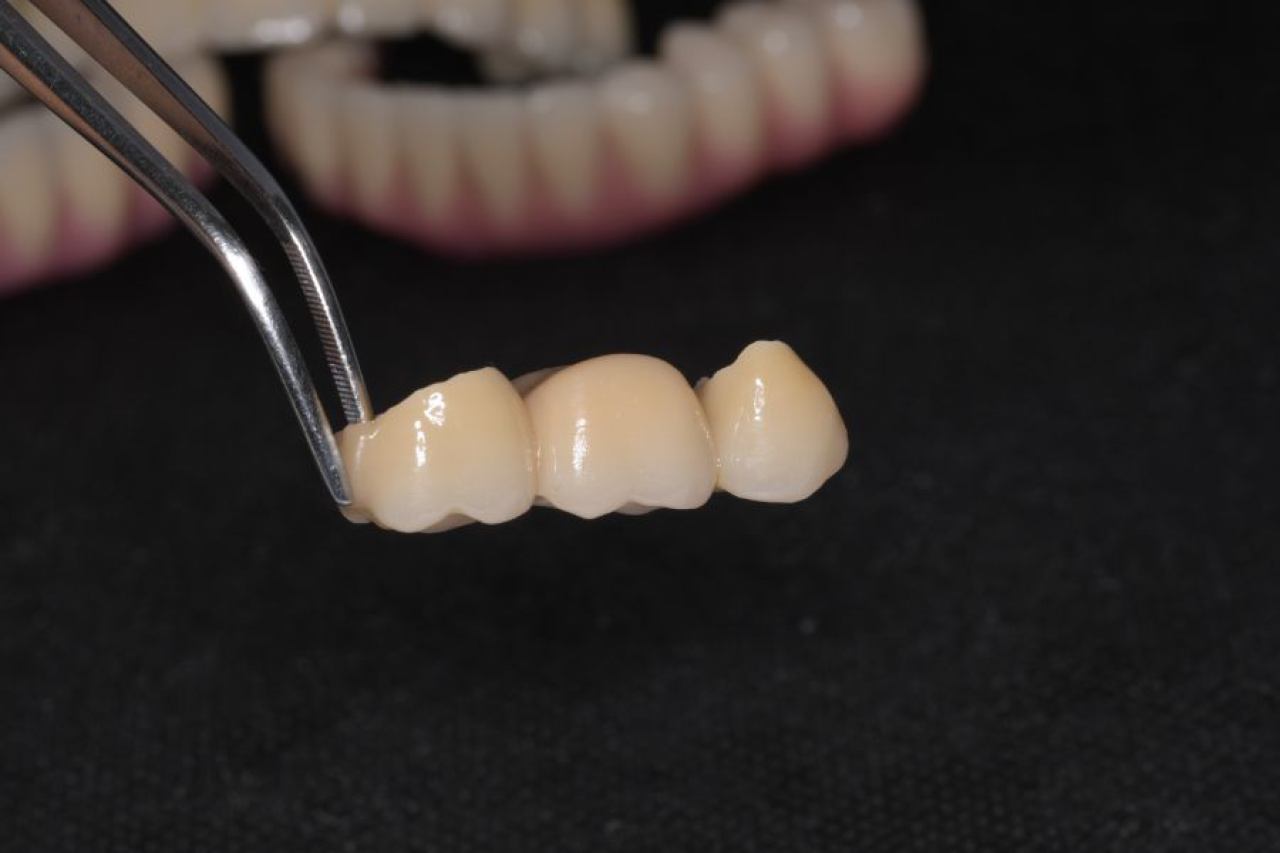

Protetika - mostovi i krunice

Dentalna protetika uključuje fiksne i mobilne radove kojima se nadoknađuje djelomična ili potpuna bezubost. Njihov cilj je povratiti funkciju žvačnog sustava i u konačnici, vrhunsku estetiku.

Marković Dental Clinic u svojoj ponudi ima metalkeramičke radove, potpunokeramičke radove, te u narodu zvane „bezmetalne", odnosno zirkonske radove.